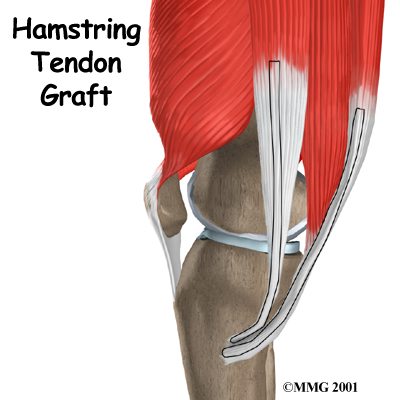

Hamstring Tendon Graft Reconstruction of the ACL

When the anterior cruciate ligament (ACL) in the knee is torn or injured, surgery may be needed to replace it. There are many different ways to do this operation. One is to take a piece of the hamstring tendon from behind the knee and use it in place of the torn ligament. When arranged into three or four strips, the hamstring graft has nearly the same strength as other available grafts used to reconstruct the ACL.